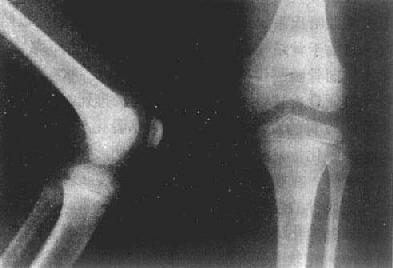

(一)小儿骨骼 长骨是软骨雏型经骨化形成的,一般有3个以上的骨化中心,一个在骨干,另外的在两端。前者为原始或一次骨化中心,后者为继发或二次骨化中心。原始骨化中心在胚胎第5周后在骨干中央发生,骨化迅速进行。出生时,长骨骨干已大部骨化,只两端仍为软骨,即骺软骨(epiphyseal cartilage)。因此,小儿长骨的主要特点是骺软骨,且未完全骨化。可分为骨干(diaphysis)、干骺端(metaphysis)、骺(epiphysis)及骺板(epiphyseal plate)等部分(图2-1-1、2)。

图2-1-2 儿童正常膝关节

3.骺 为长骨未完成发育的一端。在胎儿及儿童时期多为软骨,即骺软骨,X线片上不显影。骺软骨有化骨功能。在骨化初期于骺软骨中出现一个或几个二次骨化中心。X线表现为小点状骨性致密影。骺软骨不断增大,其中的二次骨化中心也不断由于骨化而增大,形成松质骨,边缘由不规则变为光整。

4.骺板(骺盘) 当骺与干骺端不断骨化,二者之间的软骨逐渐变薄而呈板状时,则称为骺板。因为骺板是软骨,X线片上呈横行半透明线,居骺与干骺端之间,称之为骺线(epiphyseal line)。骺板不断变薄,最后消失,即骺与骨干结合,完成骨的发育。X线表现为骺线消失。

X线上,由于软骨、关节囊都是软组织密度,不能显示,所以,相对骨端之骨性关节面间呈半透明间隙,称之为关节间隙(joint space)。因此,X线所见关节间隙包括了关节软骨及其间的真正微小间隙和少量滑液。两个相对骨端的骨性关节面光滑整齐,相距匀称,间隙清晰,宽度均匀(图2-1-4)。关节间隙的宽度因部位和年龄而异。

新生儿的关节间隙,由于骨端有骺软骨,骨化中心尚未出现或很小,而显得很宽,随着年龄增长,骺逐渐增大,则间隙逐渐变窄,待骨骼发育完成,则成为成年的宽度。